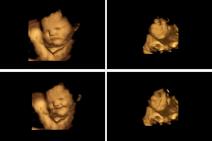

JEDE, KIJA I PLAČE: Pogledajte 4D ultrazvučni snimak koji pokazuje šta beba zaista radi u stomaku (VIDEO)

4D ULTRAZVUK: Pogledajte kako izgleda pregled i kako možete videti bebu (VIDEO)